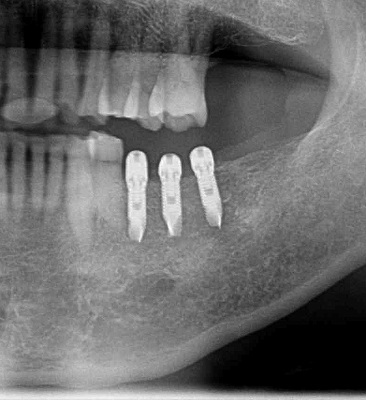

以前のブログで震災当日のことを綴りましたが、実はその日の午前中にインプラント埋入をしていたことに気付いたのです。

先日インプラントの上部構造の型取りをしたとき、ふとモニターのレントゲン写真の日付けが目に入りました。そこには、2011・3・11と入っていたのです。

「もしかして震災当日の午前中に埋入した患者さん?」となったわけです。地震があってからあまりに慌ただしかったため、当日の午前中のことはすっかり私の頭の中から抜け落ちていたのでした。もうインプラント治療が完了するくらいの時間が経っていたのですね。